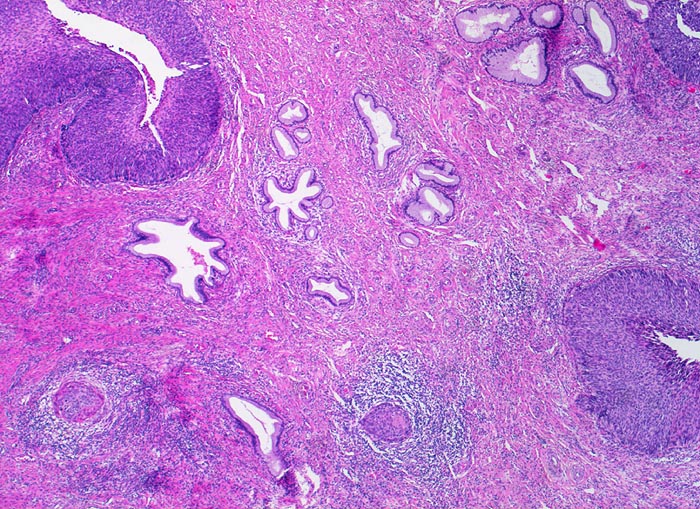

PathoPic ID 3434 - Mikroinvasives Plattenepithelkarzinom, ausgedehntes Cis

Mikroinvasives Plattenepithelkarzinom, ausgedehntes Cis

maligner Tumor

Zervix

Carcinoma in situ des metaplastischen Plattenepithels in der Umwandlungszone.

Stromainvasion.

PAP V, HPV high risk Typen

Histologie

25